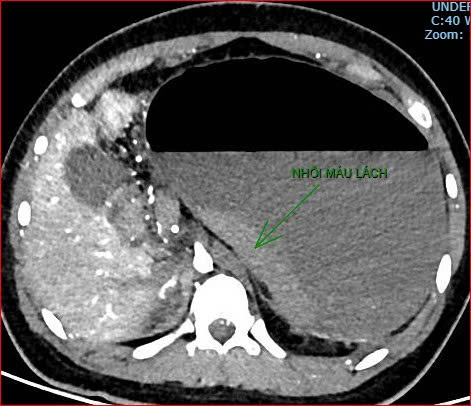

Khoảng 21 giờ 40, kết quả chụp CT cho thấy bệnh nhân rơi vào tình trạng cực kỳ nặng và hiếm gặp, bao gồm: xoắn dạ dày, nhồi máu thận trái, nhồi máu lách, viêm đầu tụy, viêm hỗng tràng, kèm dịch ổ bụng và tràn dịch màng phổi, trên nền bệnh nhân mắc hội chứng Down và tim bẩm sinh.

Hình ảnh chụp CT ổ bụng cho thấy dạ dày giãn lớn, xoắn bất thường; kèm tổn thương nhồi máu lách và viêm tụy trên nền ca bệnh hiếm, diễn biến đặc biệt nặng - Ảnh Bệnh viện cung cấp